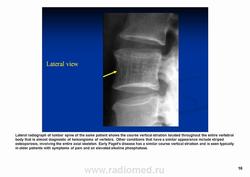

Рис.№4. Рентгенограмма грудного отдела позвоночника в боковой проекции. Определяется удовлетворительное положение костного цемента в телах Th7 и Th9 позвонков.